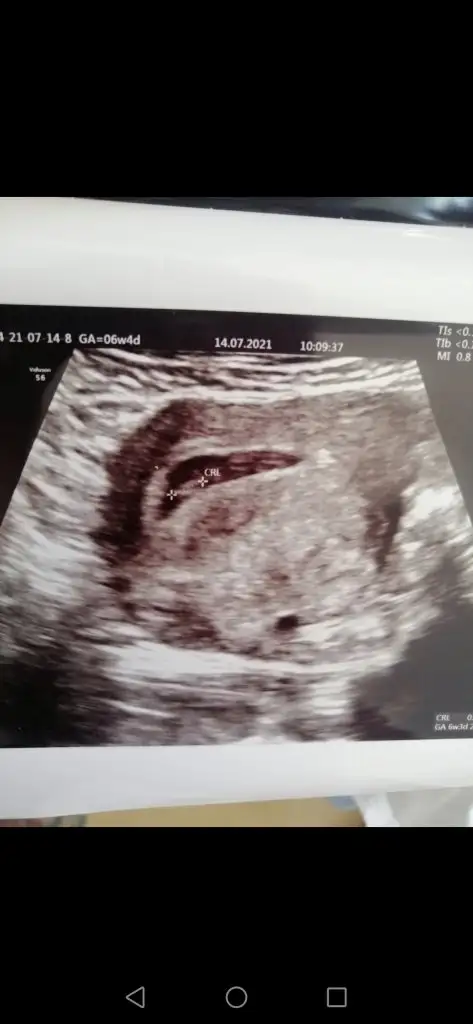

Merhaba 👋 karından ultrason 6hafta1 günlük görüntü bu şekilde 🎈bu teoriye göre ne oluyor acaba bilgisi olan yazabilir mi 🙏